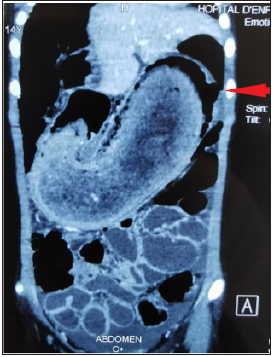

a CT scan was performed for orientation before surgical exploration (Figure 2).

Figure 2:CT image showing the gastric trichobezoard with a perforation in the fundus (arrow).

This CT revealed an enormous intragastric mass extending to the pylorus with a perforation at the level of the Fundus (Figure 2) and a peritoneal effusion of great abundance. The supraumbilical midline laparotomy revealed a huge stomach that has been pulled out of the abdomen (Figure 3). After Gastrotomy, a large J-shaped Trichobezoar was removed which had the shape of the stomach (Figure 4). After abundant washing, an ulcerative perforation was found in the gastric Fundus with several false membranes around (Figure 5). We delimited the edges with suture in 2 planes as well as a suture of the gastrotomy in 2 planes. The postoperative followup was simple, marked by an exclusively parenteral diet for 5 days with resumption of transit and progressive enteral feeding. The short and long term course was good. Child psychiatric care was instituted for our young patient.